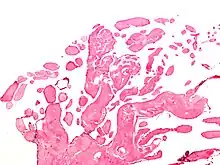

Micrograph of a papillary fibroelastoma, a benign tumor of heart valves. H&E stain.

A subset of the primary tumors of the heart are tumors that are found on the valves of the heart. Tumors that affect the valves of the heart are found in an equal distribution among the four heart valves.[2] The vast majority of these are papillary fibroelastomas. Primary tumors of the valves of the heart are more likely to occur in males. While most primary tumors of the valves of the heart are not malignant, they are more likely to have symptoms related to the valve, including neurologic symptoms and (in a few cases) sudden cardiac death.